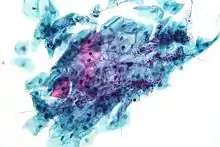

Endocervical and endometrial abnormalities can also be detected, as can a number of infectious processes, including yeast, herpes simplex virus and trichomoniasis. However it is not very sensitive at detecting these infections, so absence of detection on a Pap does not mean absence of the infection.

Micrograph of a Pap test showing trichomoniasis. Trichomonas organism seen in the upper right. Pap stain.